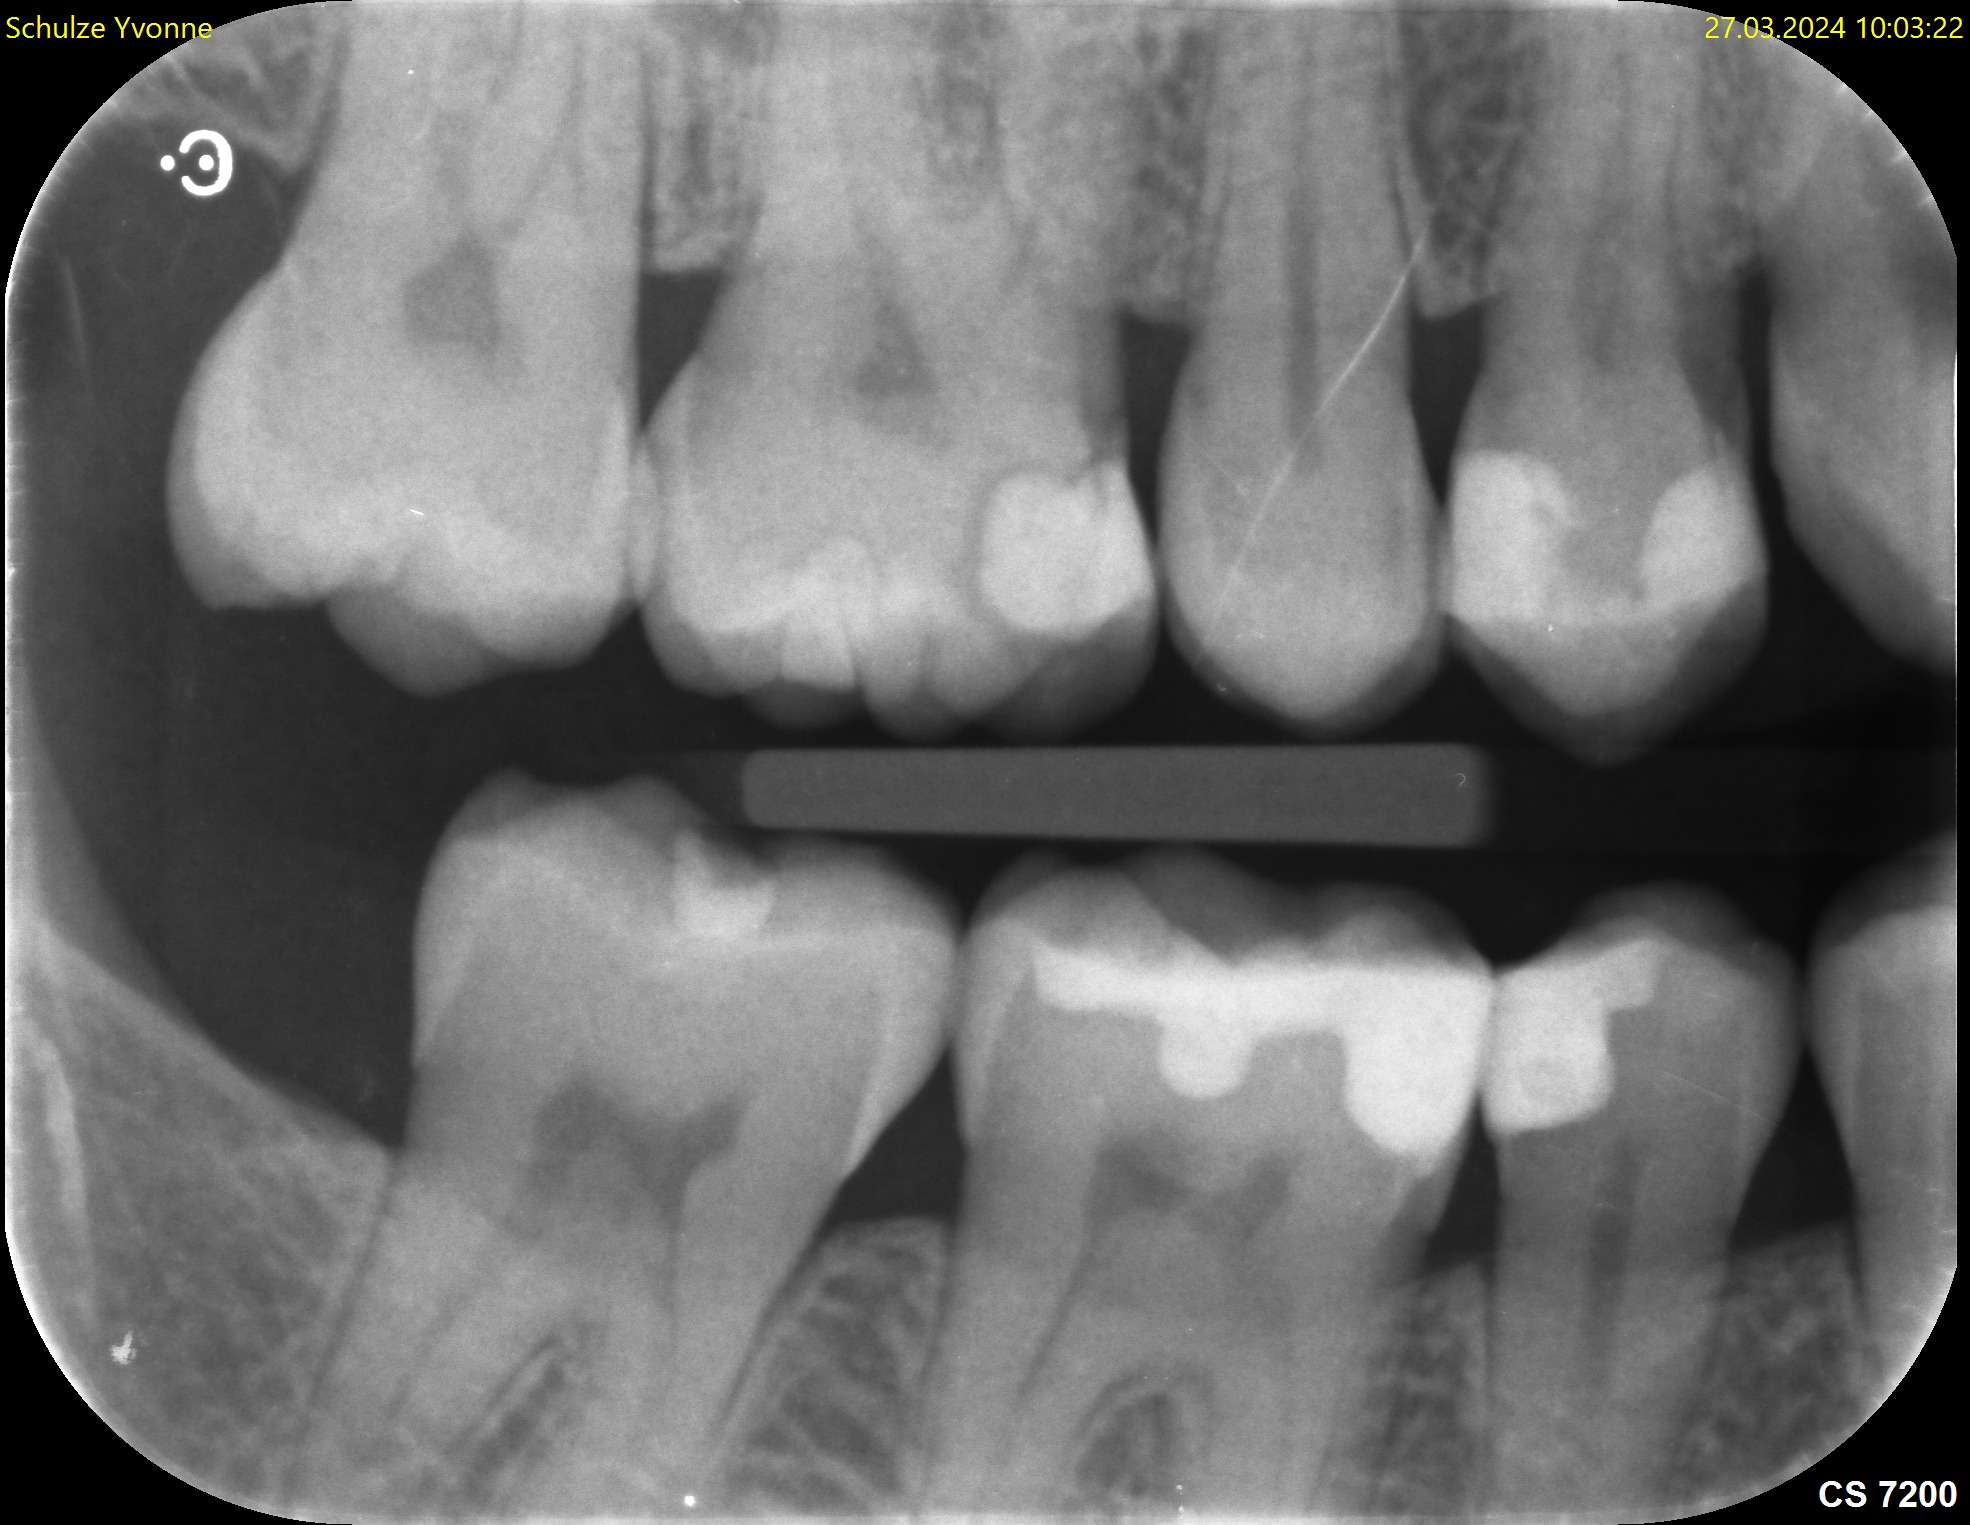

Der Zahnfilm ist eine kleine Röntgenaufnahme, die nur einen begrenzten Bereich des Kiefers zeigt – in der Regel ein bis drei Zähne mit den umgebenden Strukturen. Der Röntgenfilm oder digitale Sensor (etwa 2 × 3 cm oder 3 × 4 cm) wird dabei direkt in den Mund gelegt und vom Patienten mit dem Finger oder einer Halterung in Position gehalten.

Die Aufnahme dauert nur Sekundenbruchteile. Da der Sensor nah am Zahn liegt und der Röntgenstrahl gezielt auf einen kleinen Bereich gerichtet ist, liefert der Zahnfilm eine deutlich höhere Detailschärfe als das OPG (Orthopantomogramm). Feine Strukturen wie beginnende Karies, Wurzelkanäle oder der exakte Verlauf des Knochens an einzelnen Zähnen lassen sich präziser beurteilen.

Typische Einsatzgebiete sind die Kariesdiagnostik (besonders die sogenannten Bissflügelaufnahmen für die Zahnzwischenräume),

Die Beurteilung von Wurzelkanalfüllungen, der Verdacht auf Wurzelspitzenentzündungen, die Kontrolle nach Zahnentfernungen oder Implantationen sowie die genaue Darstellung des Knochenabbaus bei Parodontitis. Ein vollständiger Röntgenstatus aus 10 bis 14 Zahnfilmen zeigt das gesamte Gebiss in hoher Auflösung, wird aber wegen des höheren Aufwands nicht routinemäßig angefertigt.